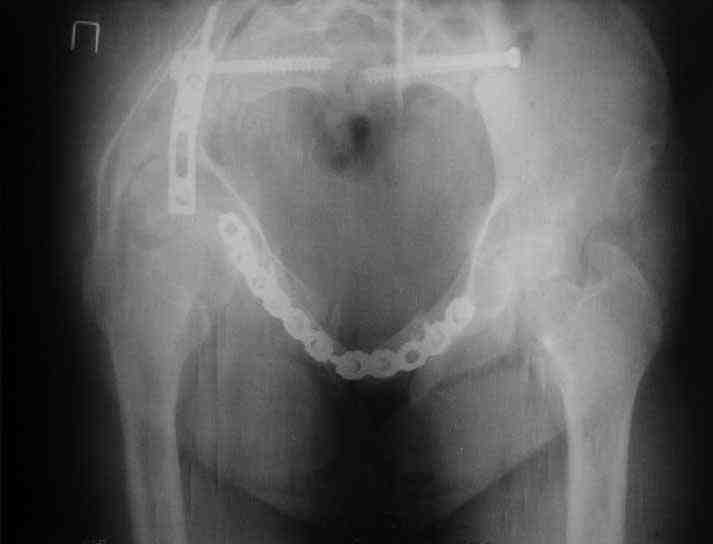

Картина на сегодня:

В настоящее время больная ходит без дополнительной опоры, боль в области таза не беспокоит, неудобств при сидении не испытывает, свободно проходит расстояние в 2-3км. Отмечается незначительная хромота, периодические боли в поясничной области низкой интенсивности, не требующие приема медикаментов, кроме того имеется вагинальный импинджемент. Срок после операции 1 год и 2 месяца.Было бы интересно услышать ваши комментарии. С уважением Агалаков М.В.